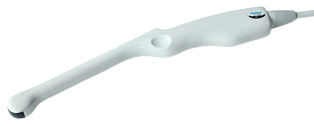

- D3C60L конвексный датчик 2.0-6.8 МГц

- D7L40L линейный датчик 4-15 МГц

- D6C15L высокочастотный конвексный датчик 4-12 МГц

- D6C12L внутриполостной конвексный ректо-вагинальный датчик 4-12 МГц

- D7L40L-REC внутриполостной линейный трансректальный датчик бок. обзором 4.0-15.0 МГц

- D6C12L внутриполостной конвексный ректо-вагинальный датчик 4.0-12.0 МГц радиус 12 мм, угол сканирования -137°

- D7C10L высокочастотный внутриполостной конвексный трансвагинальный датчик 4.0-15.0 МГц радиус 12 мм, угол сканирования -180°;